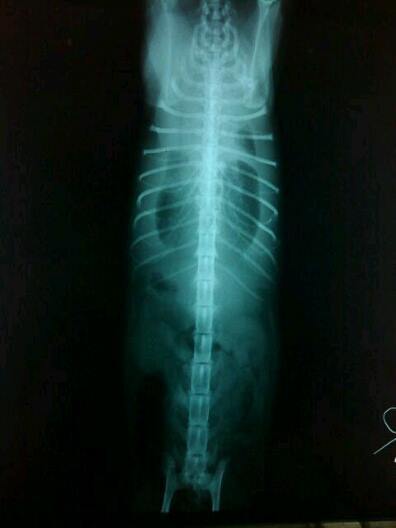

果然,助理阿姨抱著她照X光的時候就發現到,在皮毛遮蓋下的胸腔,有著大大小小數不盡的腫瘤,頓時心都涼了。

醫生說,腫瘤擴散到整個胸腔都是,且壓迫到呼吸系統,說不定癌症早已入侵骨頭,她很痛苦,別讓她再受折磨了。